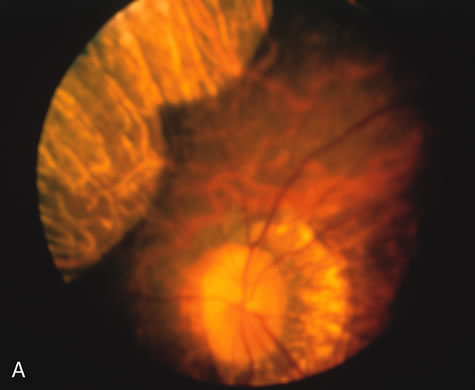

The fundus abnormalities in pigment pattern dystrophies may be subtle, especially when the pigmentary changes are orange and yellow in color. However, FA is most dramatic in highlighting these abnormalities. Thus, FA will confirm, and in some circumstances provide, the diagnosis (Fig. 11AE). Although there is no histopathologic confirmation, the fundus and angiogram suggest that an abnormal deposition of lipofuscin in the RPE is responsible for the clinical picture.

Fig. 11. Pigment pattern dystrophies. Subtle changes of the fundus in this family member with a pattern dystrophy (A) are highlighted on angiography (B). Equally dramatic is the fluorescein angiography of this young woman who presented with poor vision in association with a retinal hemorrhage (C). The angiogram reveals a bilateral, symmetric reticular pattern of the posterior pole (D, E).